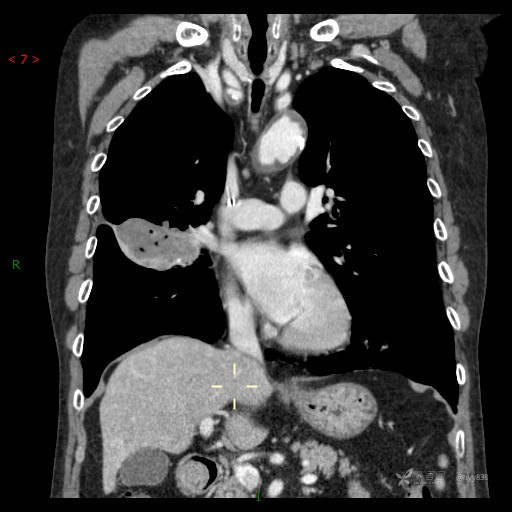

大叶性分布并低密度坏死改变,结核?真菌?肿瘤?有时候很难界定---结果公布~

讨论:影像特征?病变性质?

胸部CT肺窗